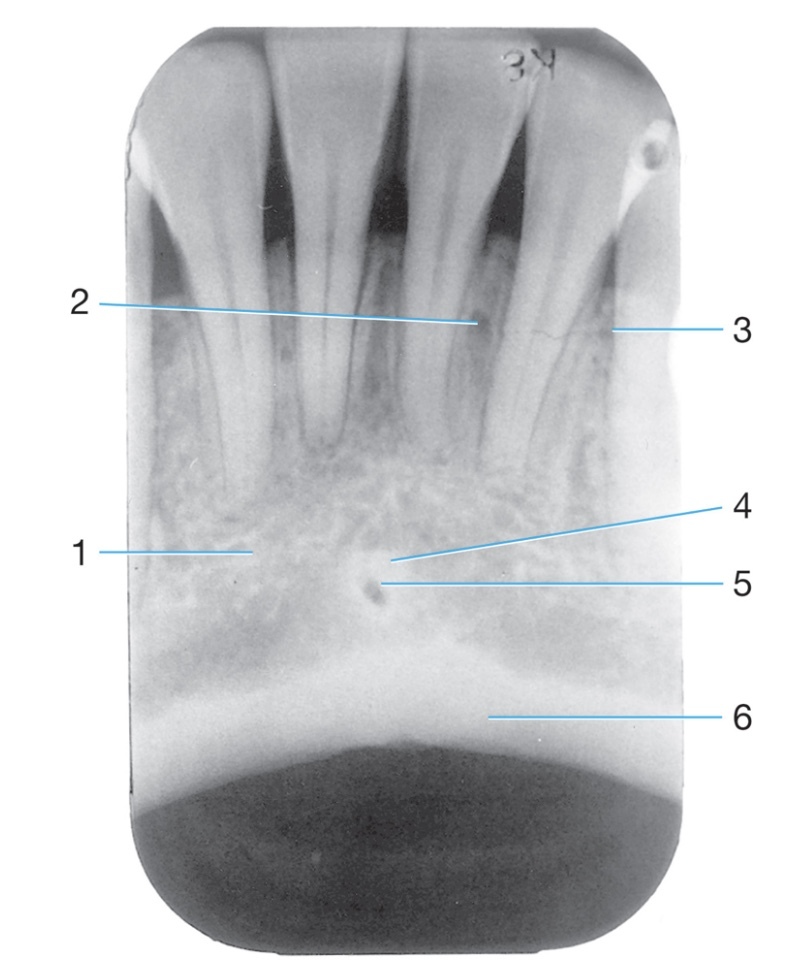

1.

Opening or hole in bone located at the midline of the anterior portion of the

hard palate directly posterior to the maxillary central incisors.

Radiolucent/Radiopaque?

Incisive foramen #1

Radiolucent

Sharp projection of the maxilla located at the

anterior and inferior portion of the nasal cavity.

Nasal Spine

Radiopaque

Identify the age of this patient

Age 8

Rounded prominence of bone that extends

posterior to the third molar region.

Maxillary Tuberosity #2

Identify #3.

Nutrient foramen